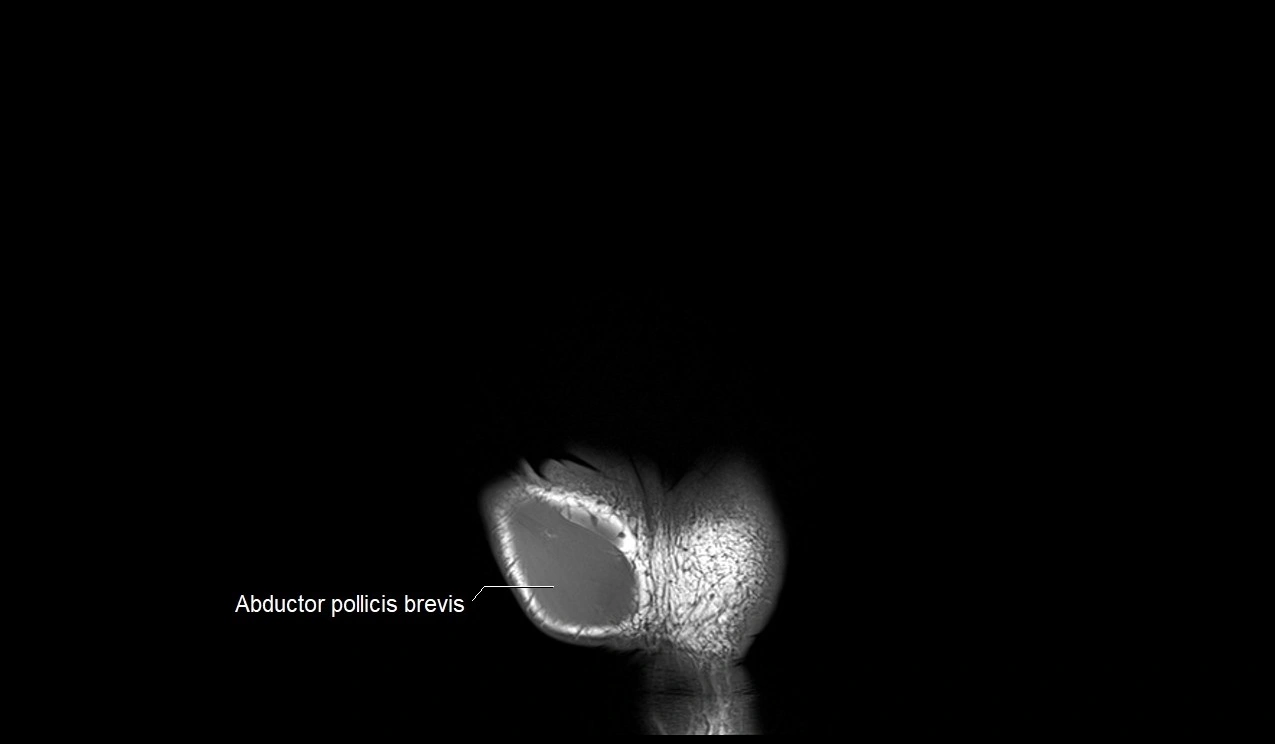

- Abductor pollicis brevis muscle